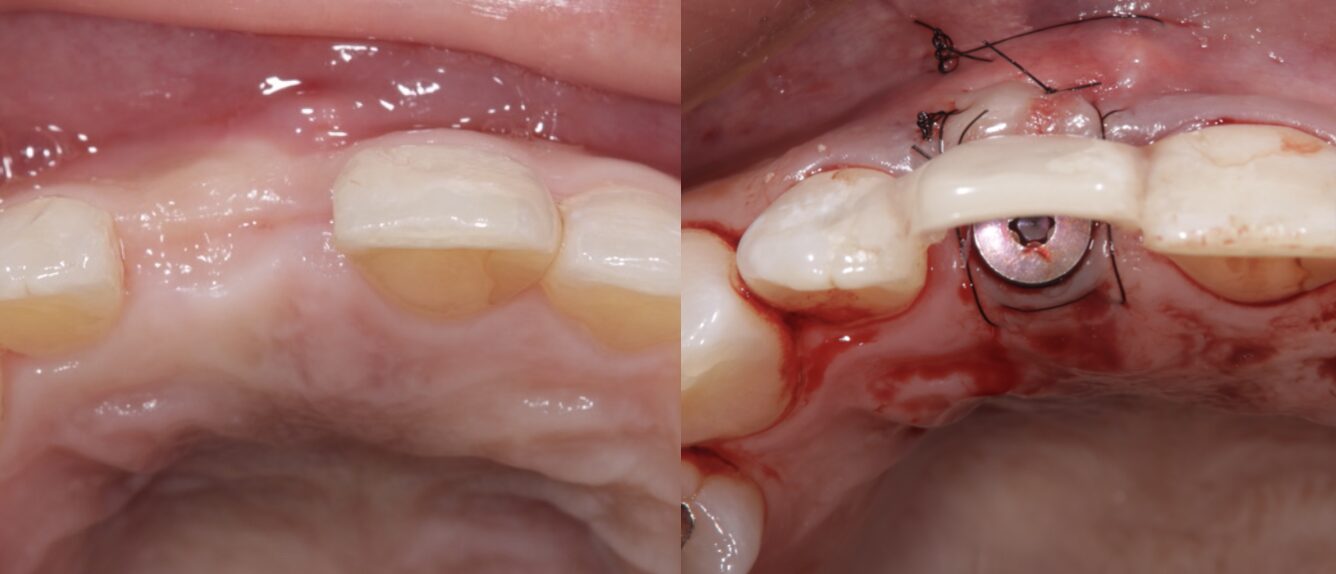

初診時の口腔内写真①

初診時の口腔内写真②

② インプラント埋入手術

抜歯後の治癒期間を経て、骨の状態を確認しながらインプラントを適切な位置と角度に埋入しました。

前歯部は見た目に大きく関わる部位のため、インプラントの位置・角度・歯ぐきの厚みを慎重に考える必要があります。

治療期間中は仮歯を使用し、見た目や日常生活への影響をできるだけ抑えながら進めました。

歯ぐきの移植を行った理由|清掃性・審美性・長期安定のために

今回の症例では、感染により骨や歯ぐきの一部が失われていました。

そのため、インプラント周囲の歯ぐきの厚みと形を整える目的で、結合組織移植術を行いました。